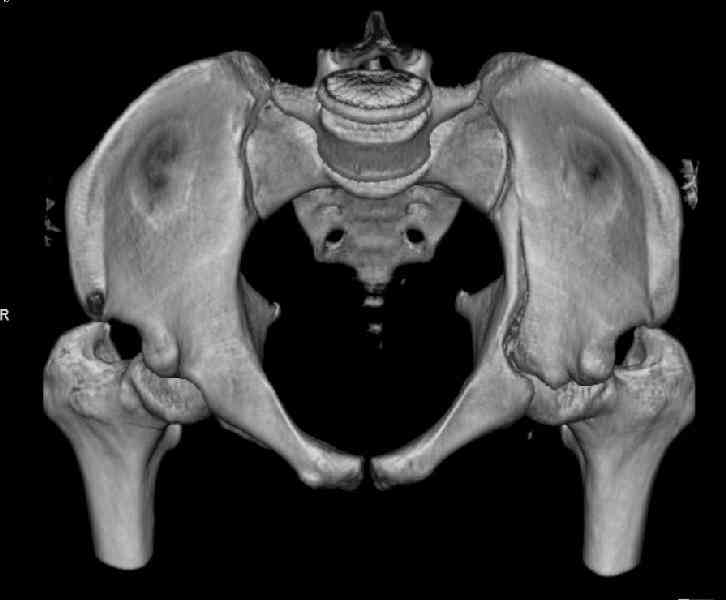

The last two images from the 3-D CT scan certainly makes the fracture look worse than the plan radiographs.

Might have to reconsider my suggestion to leave it alone at this stage.

Ilioinguinal approach would be the best to approach and clean out fracture with recon plate fixation as suggested by Dr. Venkatachalam.

Some more images. Does it help to guess which part of the acetabulum is displaced?

Normal appearing SI joints and a healed posterior column limb... my bet's on caudal segment displacement.